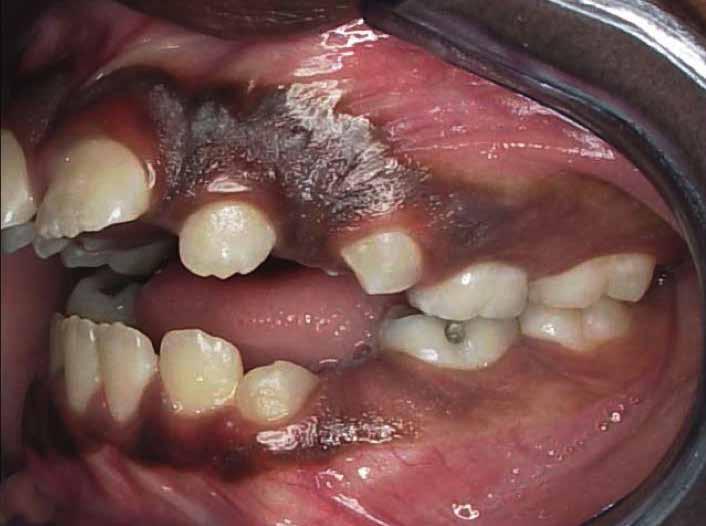

Lány páciensem I. fázisú kezelését 10 évesen kezdtük el bimaxilláris funkciós, kivehető készülékkel. Megfigyelhetőek a class 2-es eltérésnél tipikusan jellemző szűk felső és alsó fo-

gívek, valamint a nagy overjet, a mandibula disztál helyzete, továbbá a felső metszőfogak protrúziója, amelynek kialakulásához sokszor hozzájárul az ujjszopás is (1-3. képek)

A 10 éves férfi páciens a felső frontfogai késői/nem megvalósuló előtörése miatt kereste fel a rendelőnket. A klinikai és a radiológiai vizsgálat során a jobb felső nagymetszőfog impakcióját észleltük (1. ábra). A fog horizontális tengelyállással és dilacerált gyökérrel rendelkezett. A felső dentális középvonal a fogak vándorlása miatt jelentős mértékben elcsúszott. A bal felső kismetszőfog is rendkívül kedvezőtlen pozícióba került.